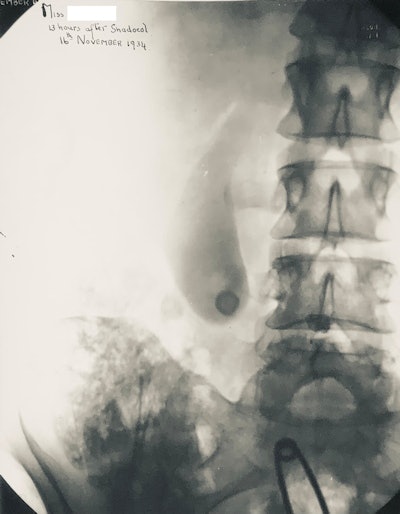

Oral cholecystogram from 1934 showing opacified gallbladder. The technique has now been replaced by ultrasound.The history of contrast media is complex and interesting, and it was fully reviewed by Christoph de Haën in what is now the definitive history of the development of contrast media.2